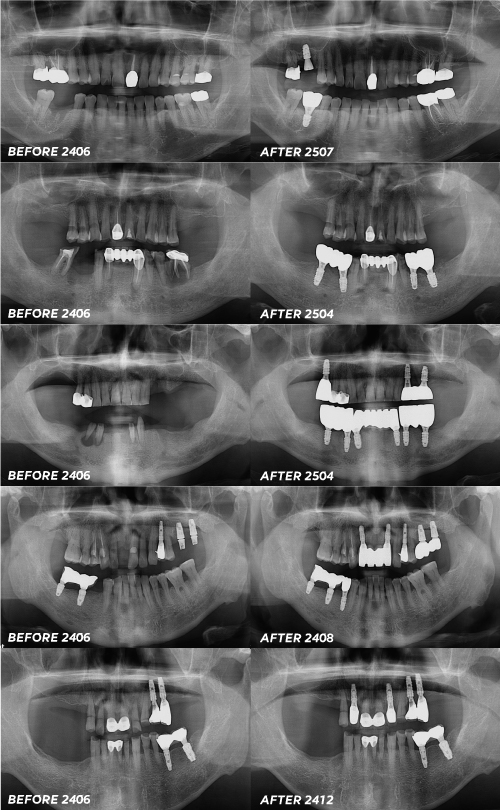

서울센텀치과 신사 임플란트 치료 사례

임플란트는 무조건 다 다시 해주는

형태의 치료가 아닙니다.

그렇기에 꼭 치과를 결정하시기 이전에

보증기간의 여부에 대해 체크해 보시고

어떤 부분에 대한 보증기간인지도 체크하고

기간은 언제까지인지 꼭 기억하여

보증기간 내 치료 받으시기를 바랍니다.

서울센텀치과 신사역은 어버트먼트, 크라운 문제시

1년 이내는 100% 무료로 진행하고 있으니

꼭 기억하시고 진료 날짜에 맞게

검진 오시길 바랍니다 :)